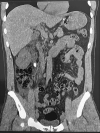

Results: Patient 1: A 58-year-old female had five episodes of acute left ureteral lithiasis in two years prior to left kidney tuberculosis. Patient 2: A 55-year-old male patient had a 1.2 cm proximal left ureteral stone and in the following six months, the diagnosis of tuberculosis was made in a nonfunctioning left kidney with ureteral thickening and stenosis. Patient 3: A 47-year-old male patient had a 1.2 cm stone in the proximal right ureter and developed urinary tuberculosis with a nonfunctioning right kidney and a contracted bladder.